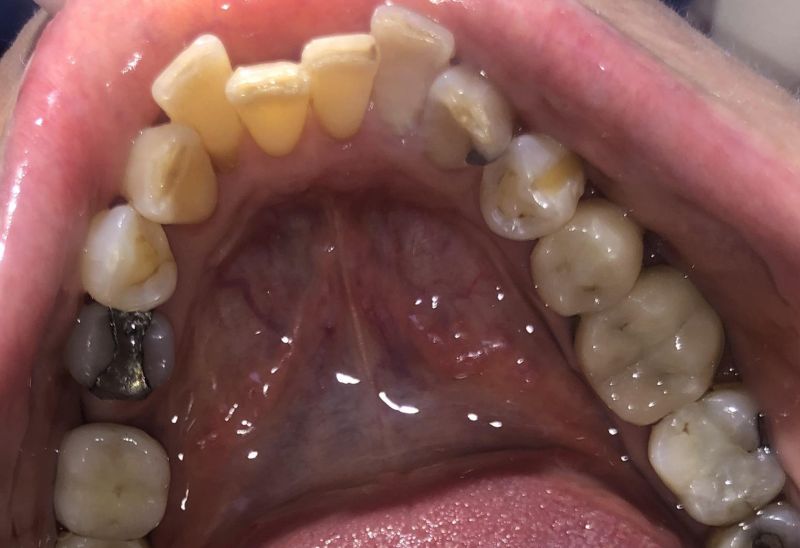

Prima e dopo l'apparecchio invisibile

In questa sezione mostreremo risultati reali ottenuti con l’ortodonzia invisibile a Roma. I cambiamenti riguardano non solo i denti, ma anche l’armonia del viso, la postura orale e l’autostima.